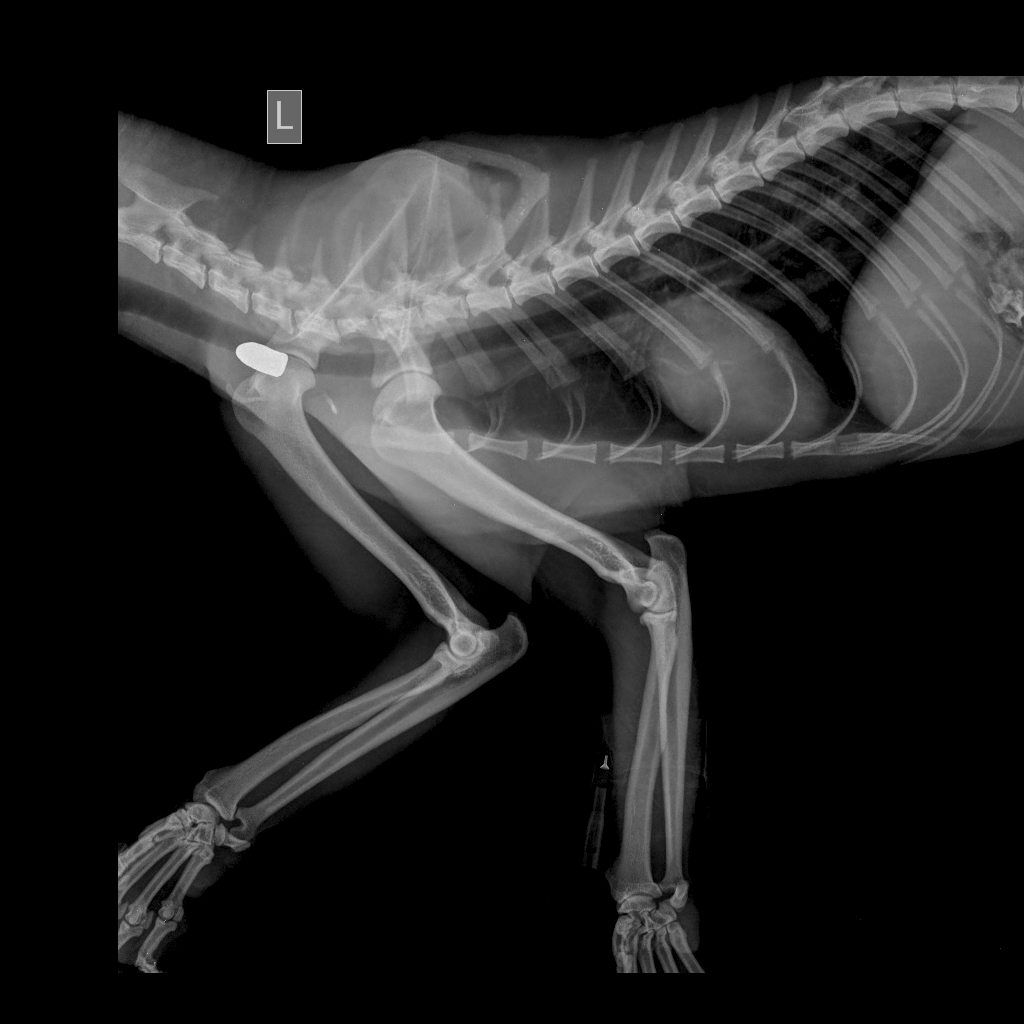

นายบรรณรักษ์ เสริมทอง ผู้อำนวยการสำนักบริหารพื้นที่อนุรักษ์ที่ 4 (สุราษฎร์ธานี) กล่าวถึงอาการของเสือลายเมฆซึ่งถูกยิงที่อุทยานแห่งชาติคลองพนม จ. สุราษฎร์ธานีว่า สัตวแพทย์ของโรงพยาบาลสัตว์เล็ก คณะสัตวแพทยศาสตร์ มหาวิทยาลัยวลัยลักษณ์ จ.นครศรีธรรมราชผ่าตัดนำหัวกระสุนที่ฝังอยู่บริเวณต้นคอ 1 ลูกออกแล้ว ทั้งนี้เจ้าหน้าที่อุทยานแห่งชาติคลองพนมได้รับแจ้งจากชาวบ้านเมื่อวันที่ 14 กุมภาพันธ์ว่า มีเสือลายเมฆบาดเจ็บนอกเขตอุทยานฯ ตรวจสอบพบ แผลบริเวณขาขวาหน้าลักษณะคล้ายรอยกระสุน ไม่สามารถขยับตัวได้ อยู่ในสภาพอิดโรย บริเวณบาดแผลเริ่มเน่า คาดได้รับบาดเจ็บมาแล้วไม่น้อยกว่า 3 วัน จึงนำส่งให้นายสัตวแพทย์ประจำสำนักฯ ซึ่งตรวจและช่วยชีวิตเสือตัวนี้ที่มีอาการน่าเป็นห่วงทั้งจากบาดแผลบริเวณไหล่ขวา รวมทั้งมีภาวะร่างกายขาดน้ำและซูบผอม จึงส่งตัวต่อไปรักษาต่อที่โรงพยาบาลสัตว์เล็กฯ เมื่อผ่าตัดแล้ว ยังคงต้องรักษาต่อด้วยการให้ยาลดอักเสบและยาฆ่าเชื้อจนกว่าจะพ้นขีดอันตราย จึงจะดำเนินการตามขั้นตอนการดูแลรักษา แล้วปล่อยคืนสู่ธรรมชาติในถิ่นที่อยู่อาศัยเดิมต่อไป

ด้านนายสัตวแพทย์ปิยะ เสรีรักษ์ นายสัตวแพทย์ประจำสำนักบริหารพื้นที่อนุรักษ์ที่ 4 (สุราษฎร์ธานีั) กล่าวว่า เสือลายเมฆตัวนี้เป็นเพศเมีย ขนาดตัวเต็มวัย ขณะนี้ยังไม่พ้นขีดอันตราย โดยสัตวแพทย์ที่รักษาตรวจสอบเพิ่มเติมพบว่า มีอาการสมองบวมที่สันนิษฐานว่า ตกจากที่สูง อีกทั้งขาดน้ำรุนแรงจากการไม่กินอาหารหลายวันหลังถูกยิง นอกจากนี้ยังพบว่า ตาบอดสนิทจากการติดเชื้อติดเชื้อเฮอปีสร์ไวรัสมาก่อนหน้า เมื่อประเมินจากสภาพตอนนี้ ที่ยังฟื้นจากยาสลบไม่ดี สภาพแผล รวมถึงแนวโน้มเม็ดเลือดขาวที่ต่ำจากการติดไวรัสที่ทำให้ภูมิคุ้มกันตก มีโอกาสติดเชื้อในกระแสเลือดสูง ขณะนี้ให้ยาปฏิชีวนะเพื่อควบคุมการติดเชื้อแบคทีเรียแทรกซ้อน แต่ต้องหายากระตุ้นภูมิคุ้มกันให้ร่างกายสามารถกำจัดเชื้อไวรัสได้ โอกาสรอดชีวิตมีเพียง 20% ให้น้ำเกลือตลอด แต่ไม่ค่อยตอบสนอง แพทย์ดูแลรักษาใกล้ชิด หากผ่านพ้น 10 วันไปได้ จึงจะมั่นใจว่า ปลอดภัย . – สำนักข่าวไทย